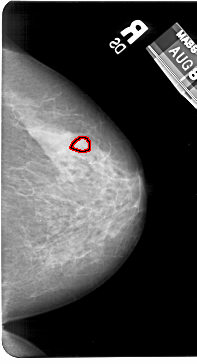

FILE: A_1602_1.RIGHT_MLO.OVERLAY

TOTAL_ABNORMALITIES 1

ABNORMALITY 1

LESION_TYPE MASS SHAPE LOBULATED MARGINS OBSCURED

ASSESSMENT 4

SUBTLETY 2

PATHOLOGY BENIGN

TOTAL_OUTLINES 1

BOUNDARY